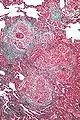

Low magnification view of the histology of chronic hypersensitivity pneumonitis. The interstitium is expanded by a chronic inflammatory infiltrate. Two multinucleated giant cells can be seen within the interstitium at left, and a plug of organizing pneumonia at bottom left.

Lung biopsies can be diagnostic in cases of chronic hypersensitivity pneumonitis, or may help to suggest the diagnosis and trigger or intensify the search for an allergen. The main feature of chronic hypersensitivity pneumonitis on lung biopsies is expansion of the interstitium by lymphocytes accompanied by an occasional multinucleated giant cell or loose granuloma.[12][13]

When fibrosis develops in chronic hypersensitivity pneumonitis, the differential diagnosis in lung biopsies includes the idiopathic interstitial pneumonias.[14] This group of diseases includes usual interstitial pneumonia, non-specific interstitial pneumonia and cryptogenic organizing pneumonia, among others.[12][13]